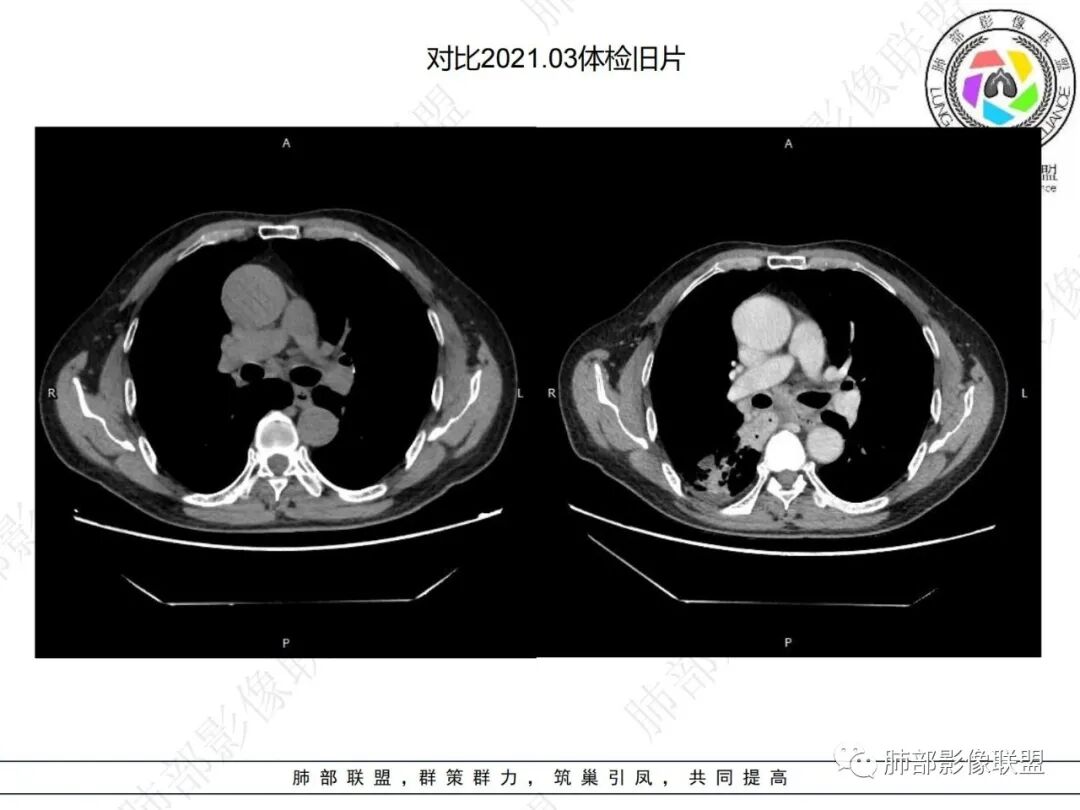

对比患者3月份的CT图,原隆突下存在增大钙化淋巴结,现在出现气体影,且钙化显示不清,应想到淋巴结结核破溃成瘘可能性。